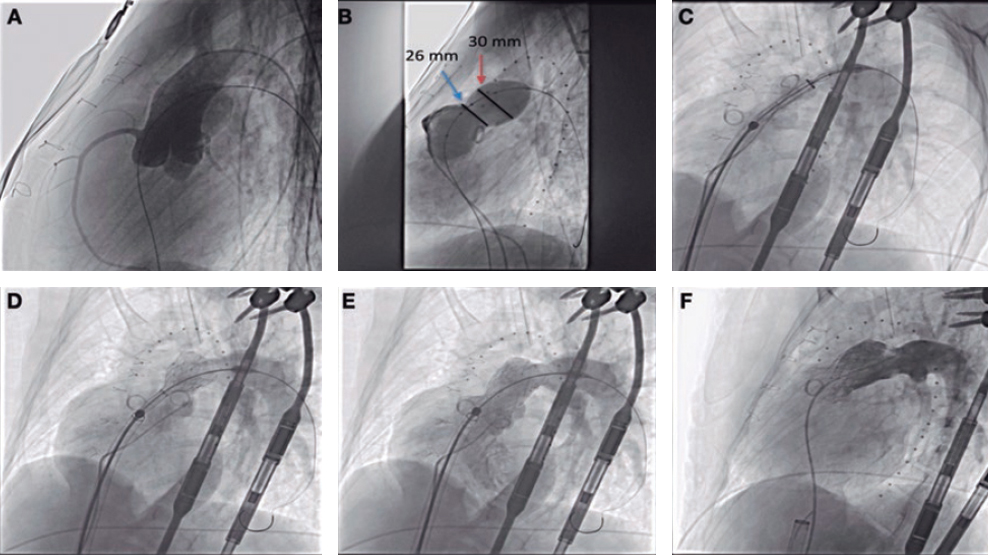

8. Back in the RV, the perpendicularity of the clip with respect to the target coaptation line should be confirmed on the transgastric short axis view. Then, the grasping view should be looked for, that is, the view that better shows the target leaflets and the clip with wide open arms. It is essential to have good ultrasound imaging during grasping to guarantee the correct insertion of the leaflets and the perpendicularity of the arms of the clip. Repeated suboptimal captures of the leaflets should be avoided to not cause excessive damage (TV leaflets are thinner and more fragile compared to the mitral valve leaflets) (figure 7).

Figure 7. Examples of grasping view. A and D: patient 1, grasping from the intercommissural view at 75° and from the direct grasping view at 125°. B and E: patient 2, direct grasping view acquired at 0° and 160°. C and F: right, anterior, oblique projection to steer the movement of the clip. A, anterior; S, septal.